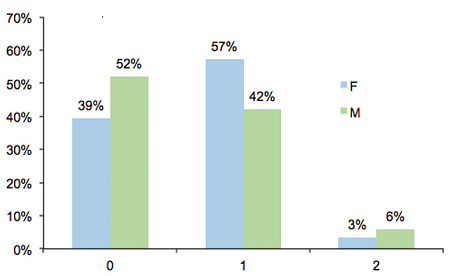

El número de lesiones por sujeto varió entre 0 y 2. El 49% de los sujetos de la muestra presentó una sola lesión, no encontrándose diferencias significativas por género. El 57% de las niñas tuvo una sola lesión, mientras que la proporción fue menor en los niños (42%) (diferencia no significativa, valor-p = 0.4093). El 5% de la muestra presentó dos lesiones, sin observarse diferencias significativas entre los géneros (3% niñas, 6% niños). El número de lesiones por sujeto se presenta en la Figura 2.